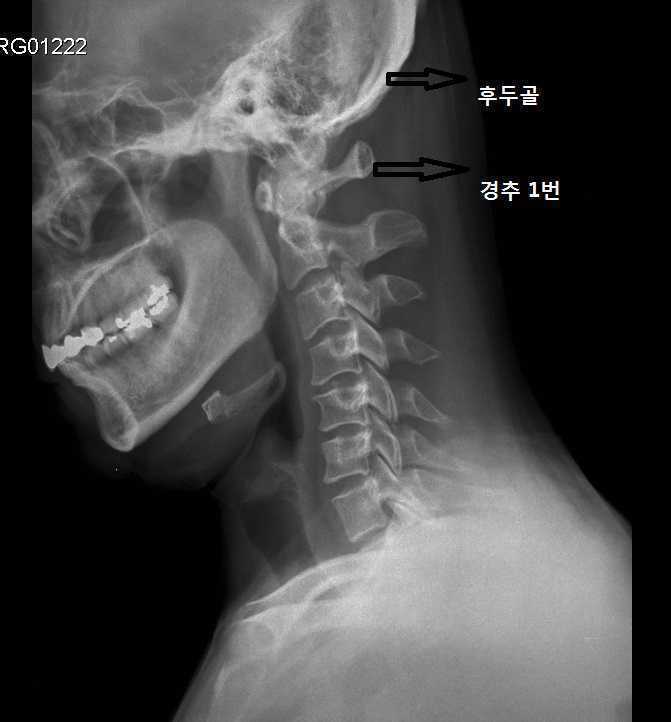

• 둘째, 턱 관절의 근육을 긴장시키는 주된 원인이 턱관절 그 자체에 많은 경우는 내재적으로 치과적 문제를 가지고 있거나 관절상태 자체에 퇴행변화를 가져오는 경우를 제외하고는 대개 상부 경추의 이상으로 인한 2차적 긴장 형태가 주를 이룹니다. 따라서 상부 경추만 잘 치료해도 턱 관절의 긴장은 상당 부분 해소됩니다.

• 셋째, 관절은 원래의 가동성이 어느 것이 더 좋으냐를 따져봐야 하는데 턱 관절보다는 상부경추의 가동성이 훨씬 적기 때문에 관절이 묶일 때는 상부경추가 더 쉽게 묶이는데 반해 턱 관절은 기본적인 가동성이 매우 좋기 때문에 관절 자체가 묶이기는 쉽지 않습니다.